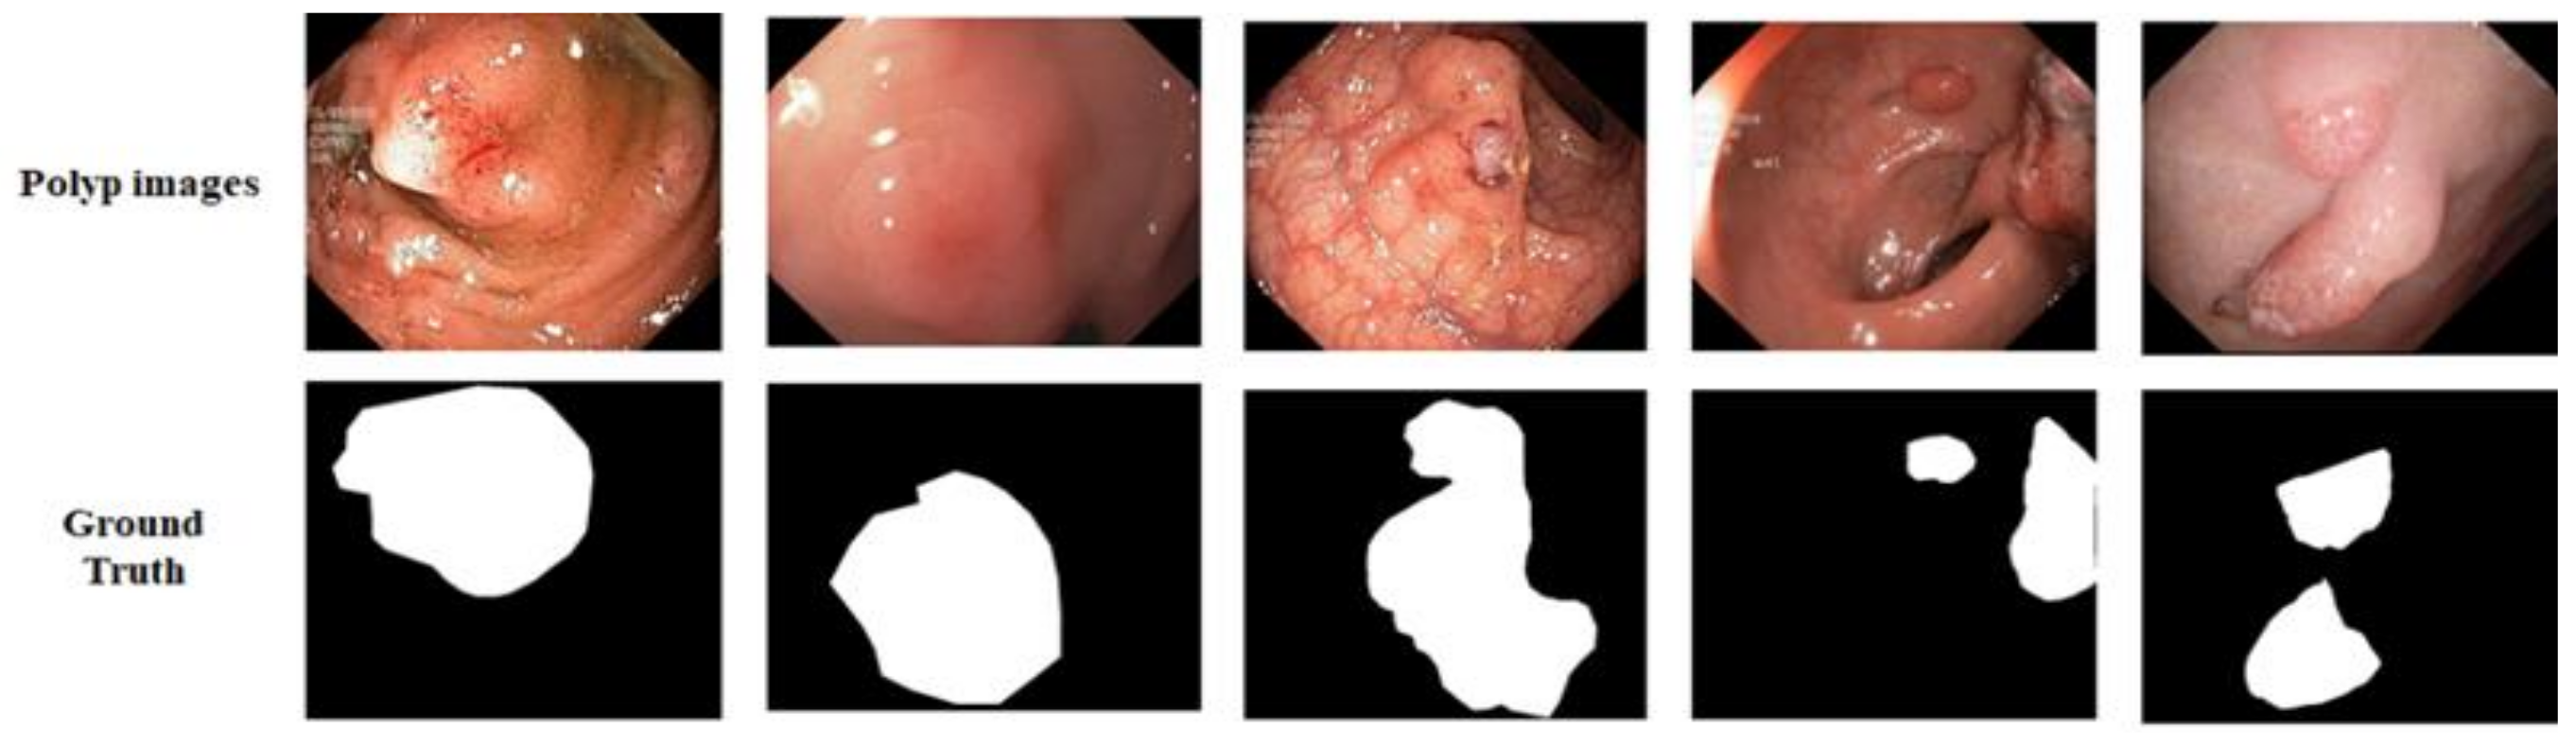

Kvasir-SEG: We utilized the Kvasir-SEG dataset [48], which has 1000 polyp images and their corresponding ground truth masks annotated by professional gastroenterologists from Vestre Viken Health Trust in Norway, as shown in Figure 5. The images have sizes ranging from 332 × 487 to 1920 × 1072 pixels, but training and testing were performed with an image resolution of 224 × 224 pixels. The images were randomly split into 80% for training, 10% for validation, and 10% for testing.

Figure 5. Example of data from Kvasir-SEG dataset. The first row shows original images and the second row presents their respective ground truth.